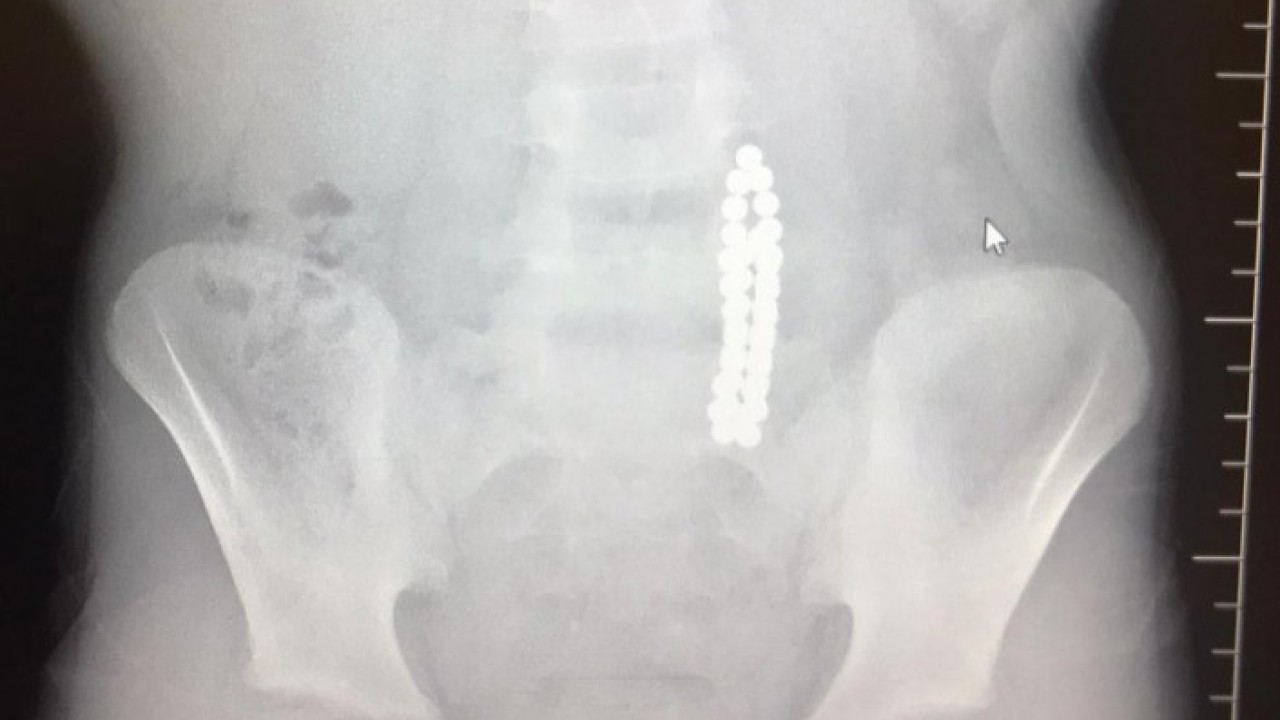

İstanbul Beylikdüzü'nde 9 yaşındaki bir çocuk ailesinin haberi olmadan neodyum adı verilen stres bilyeleri olarak da bilinen 42 adet mıknatısı yuttu. Birkaç gün sonra şiddetli karın ağrısı ve kusma şikayeti ile hastaneye gelen çocuğun röntgeni çekildi.

Röntgen filminde çocuğun midesinde boncuklar halinde yabancı bir cisim tespit edildi. Bağırsağını delen cismi fark eden Beykent Üniversitesi Çocuk Cerrahisi Uzmanı Prof. Dr. Ali Çay çocuğu ameliyata aldı. Yapılan ameliyatta çocuğun bağırsaklarından rengarenk şekilde 42 adet neodyum çıkarıldı.

Konuyla ilgili konuşan Prof. Dr. Çay, yutulan cisimlerin normalde sindirim sistemi ile çıkabileceğini ancak çoklu mıknatısların bağırsaklarda delinmeye neden olabileceğini ifade ederek, "Bizim hastamız yaklaşık 42 tane bu mıknatıstan yutmuş çeşitli hastanelere müracaat etmiş. Burada yapılan incelemelerde çekilen filmlerde tesadüfen bu mıknatısları yuttuğunu biz radyografide gördük hastamızı ameliyata aldık. İnce bağırsak uç kısmında delinme oluşturmuştu. Biz bu mıknatısları çıkardık" dedi.